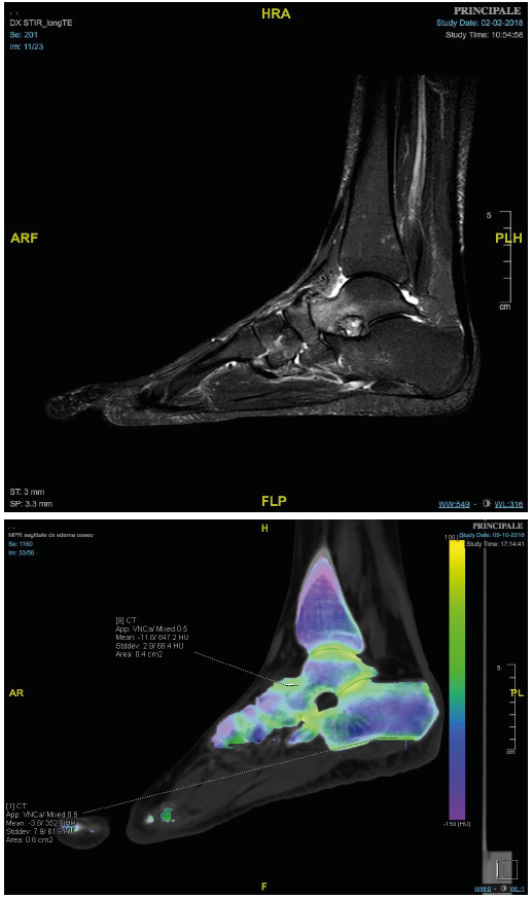

La XAI permette di visualizzare, ad esempio, quali aree di un’immagine medica hanno influenzato la decisione di un sistema diagnostico, o quali parametri clinici hanno pesato maggiormente nel predire una patologia. In questo modo, il medico non è sostituito, ma accompagnato: l’intelligenza artificiale diventa un secondo parere, non un giudice invisibile.